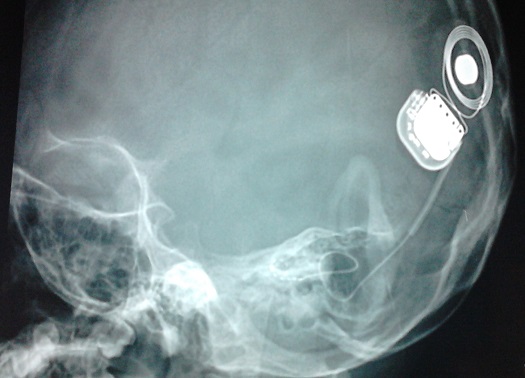

Hình ảnh X Quang Ốc tai điện tử đã được phẫu thuật cấy vào bệnh nhân Diễm My (hình trái) và Anh Thư (hình phải)